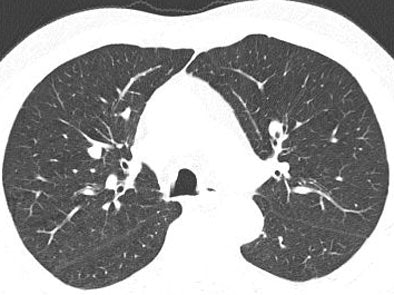

The study looked at 20 datasets selected from patients with known intrapulmonary nodules. Images were acquired on a Siemens Somatom 16 scanner at 120 kVp, effective 100 mAs, 16 x 1.5-mm collimation, 2-mm-thick sections with 1.5-mm reconstruction intervals, and with a standard lung reconstruction kernel.

The raw data were processed by artificial noise software to simulate exposure using 10 effective mAs before being run through the CAD, and the results compared. Image noise was quantified by measuring the standard deviation in Hounsfield units of a syringe placed on the patient's sternum during imaging.

In all, 113 nodules (one to 13 nodules per case, average six; average size 78 mm3) were found by a consensus panel of two experienced radiologists with access to all imaging and CAD data.

Compared with the expert readers, standard-dose CAD had an overall sensitivity of 77.6%, with a per-patient sensitivity of 84% and 1.8 average false positives per case. At the low-dose settings, CAD found 64 nodules for an overall sensitivity of 55% with a per-patient sensitivity of 67% and 1.5 false-positives per case. Interestingly, Das said, there was no statistically significant difference in false positives between the two settings.

![]() |

| The marked nodule (green) was deemed not clinically relevant. However, CAD detected it only at the full-dose setting, and not at low-dose (10 mAs). Image courtesy of Dr. Marco Das. |

Most nodules missed on CAD at the low-dose settings were smaller than 6 mm, he said.